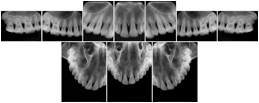

Intra-oral radiography typically involves acquisition of multiple images of various parts of the dentition. Many digital radiographic systems offer customized templates that are used for displaying the images in a study on the screen. These templates may also be referred to as mounts or view sets. The Structured Display Object represents a standard method of encoding and exchanging the layout and intended display of Structured Displays. A structured display object created in this manner could be stored with a study and exchanged with images to allow for complete reproduction of the original exam.

3. A dental provider wishes to capture a series of DICOM IO images for the patient’s dentition. The tooth morphology, teeth are divided into molars, premolars, canines and incisors, and a number of images for each jaw. The anatomic information was captured utilizing the triplet of schema. This standard code sequence is based on ISO 3950-2010, Dentistry - Designation system for teeth and areas of the oral cavity.

In most standard cases, images are oriented in structured layouts. These structured displays are useful to be shared between providers for reference purposes.

Table OO.1.1-1 shows structured display standard templates, where Viewset ID is based on the Japanese Society for Oral and Maxillofacial Radiology (JSOMR) classification provided by JIRA (Japan Medical Imaging and Radiological Systems Industries Association, www.jira-net.or.jp). Expected or typical teeth to be imaged location, region and designation codes are based on ISO 3950-2010, Dentistry - Designation system for teeth and areas of the oral cavity. For all the hanging protocols listed in OO.1.1-1, the value to use for Hanging Protocol Creator (0072,0008) is "JSOMR" and the value to use for Hanging Protocol Name (0072,0002) does not include "JSOMR" (e.g., "DL-S001A", not "JSOMR DL-S001A").